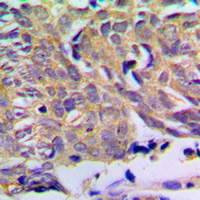

IHC (Immunohiostchemistry)

(Immunohistochemical analysis of PXMP2 staining in human prostate cancer formalin fixed paraffin embedded tissue section. The section was pre-treated using heat mediated antigen retrieval with sodium citrate buffer (pH 6.0). The section was then incubated with the antibody at room temperature and detected using an HRP conjugated compact polymer system. DAB was used as the chromogen. The section was then counterstained with haematoxylin and mounted with DPX.)